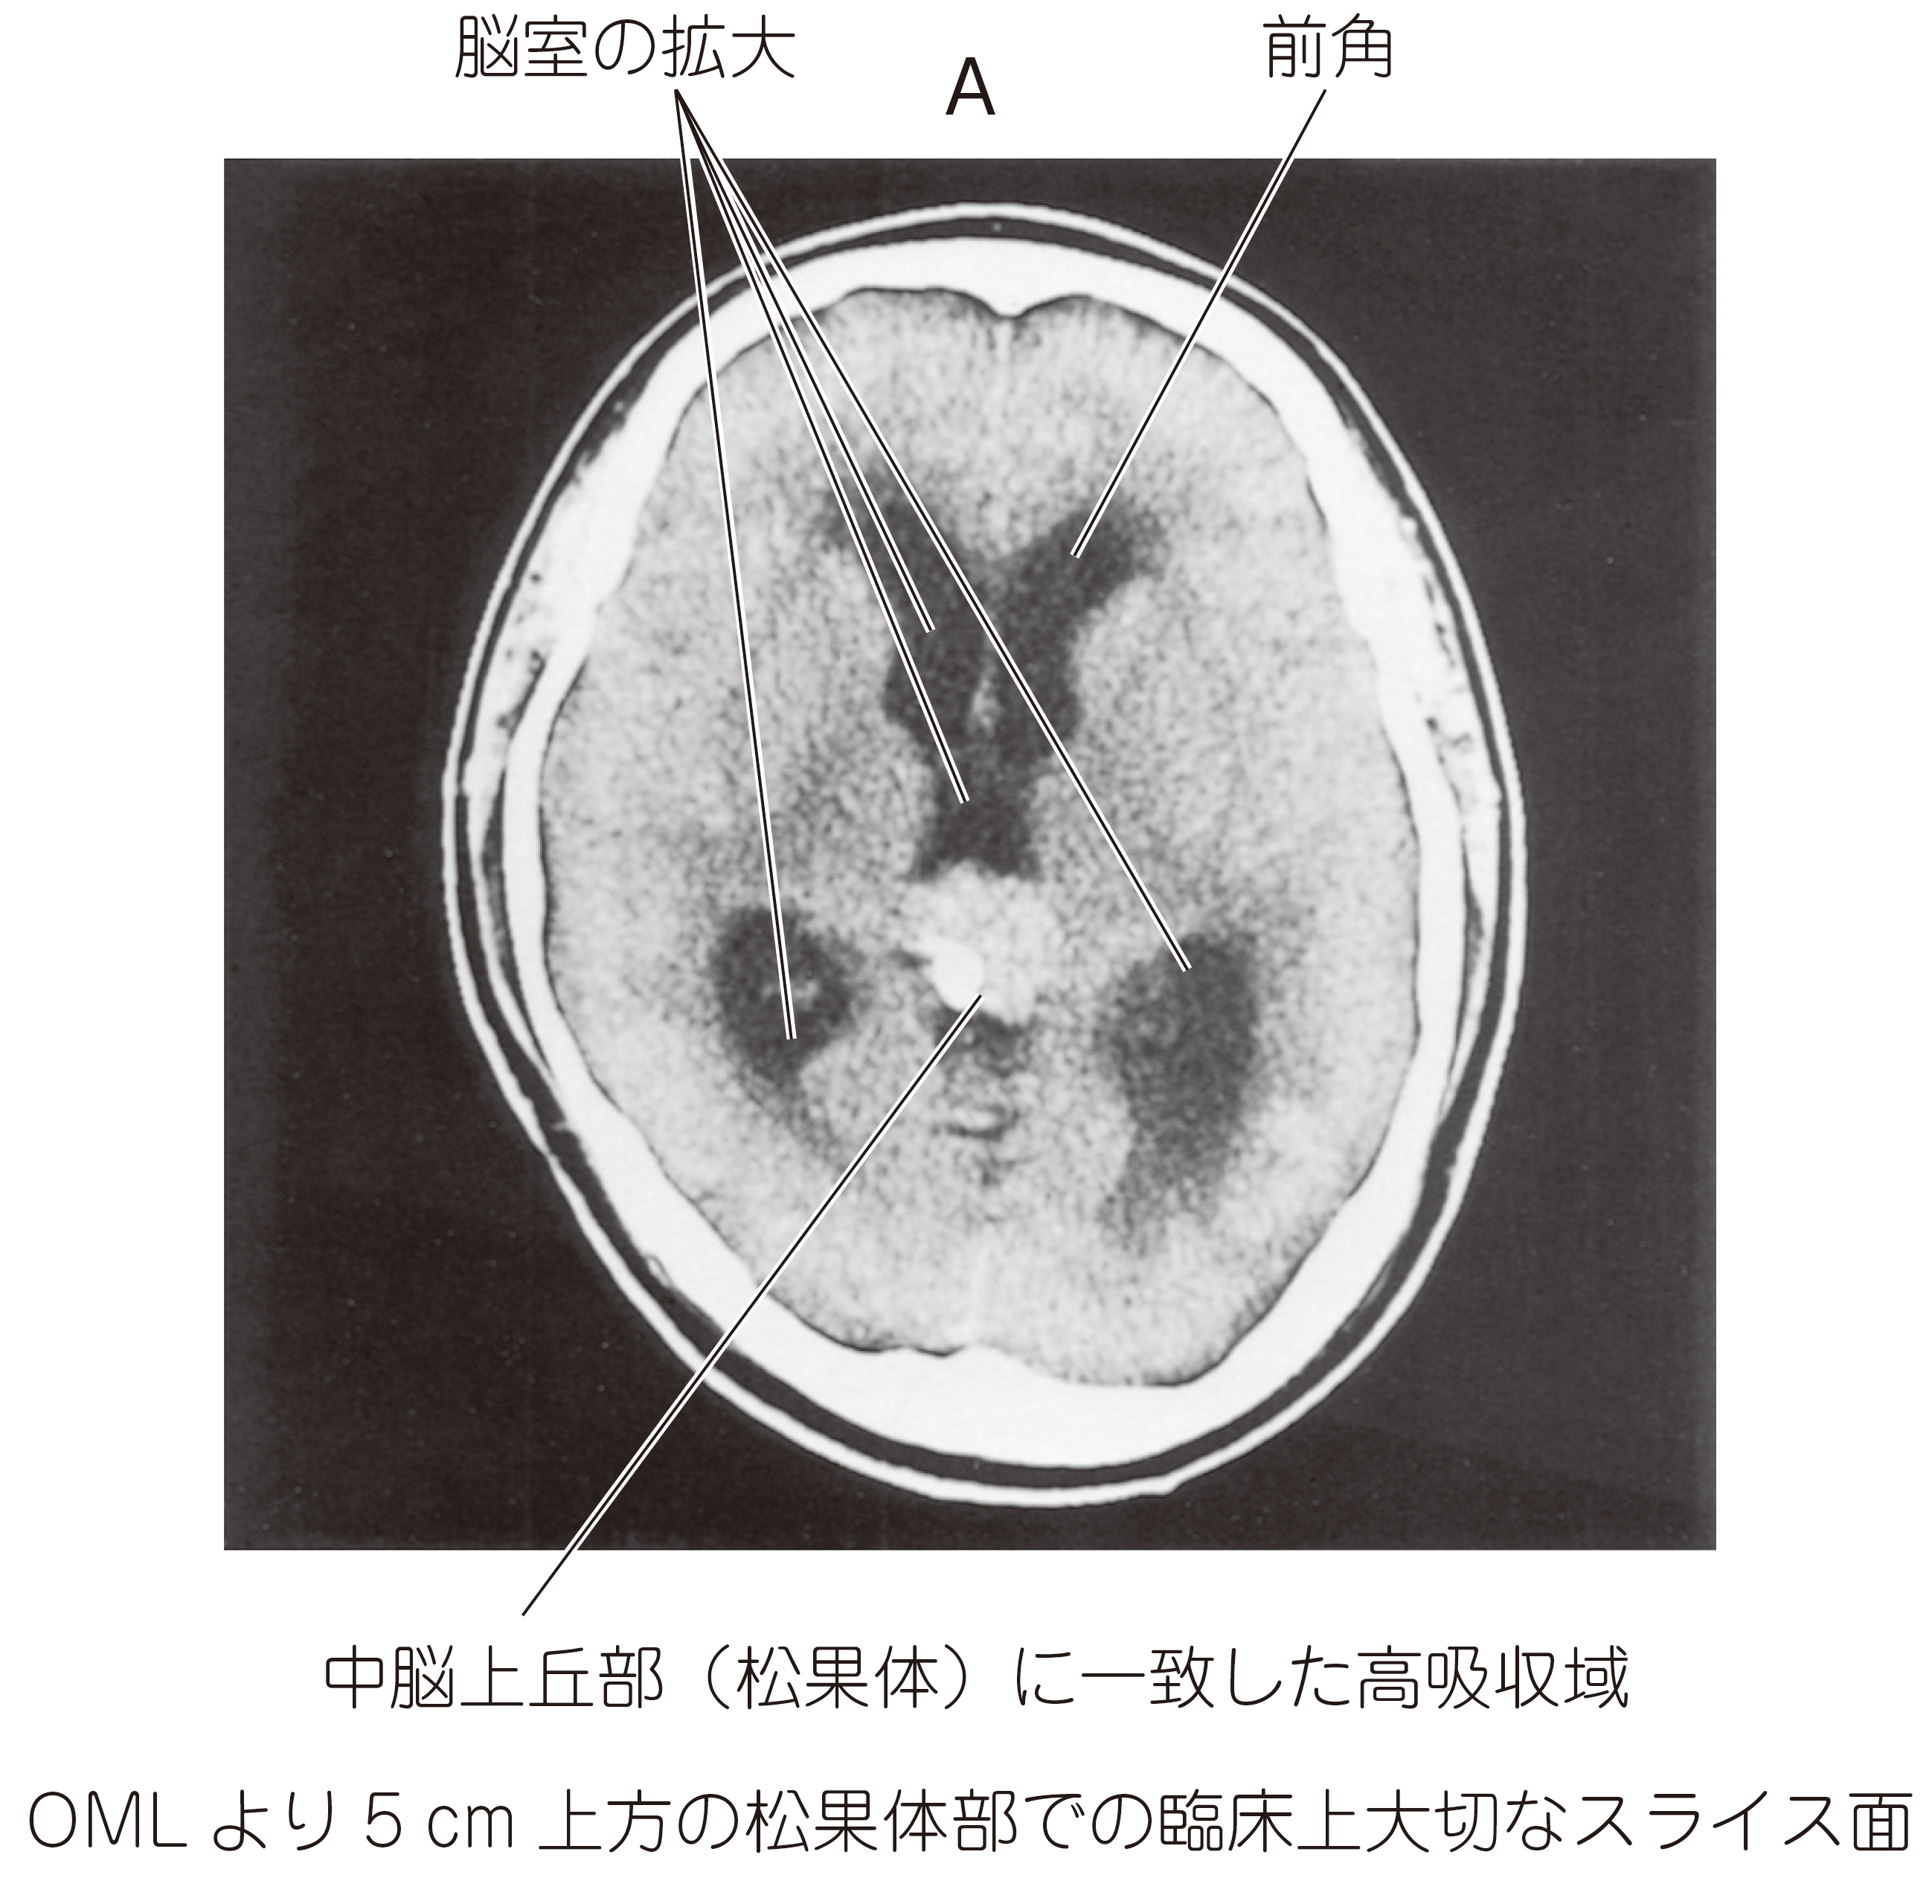

19歳の男性。嘔吐,頭痛を主訴とし,独歩で来院した。両側眼底のうっ血乳頭と上方注視障害とがあった。水頭症に対するシャント手術後に放射線治療を開始した。放射線治療開始前と20Gy照射後の頭部エックス線単純CT(AB)を示す。

画像診断

上画像参照。